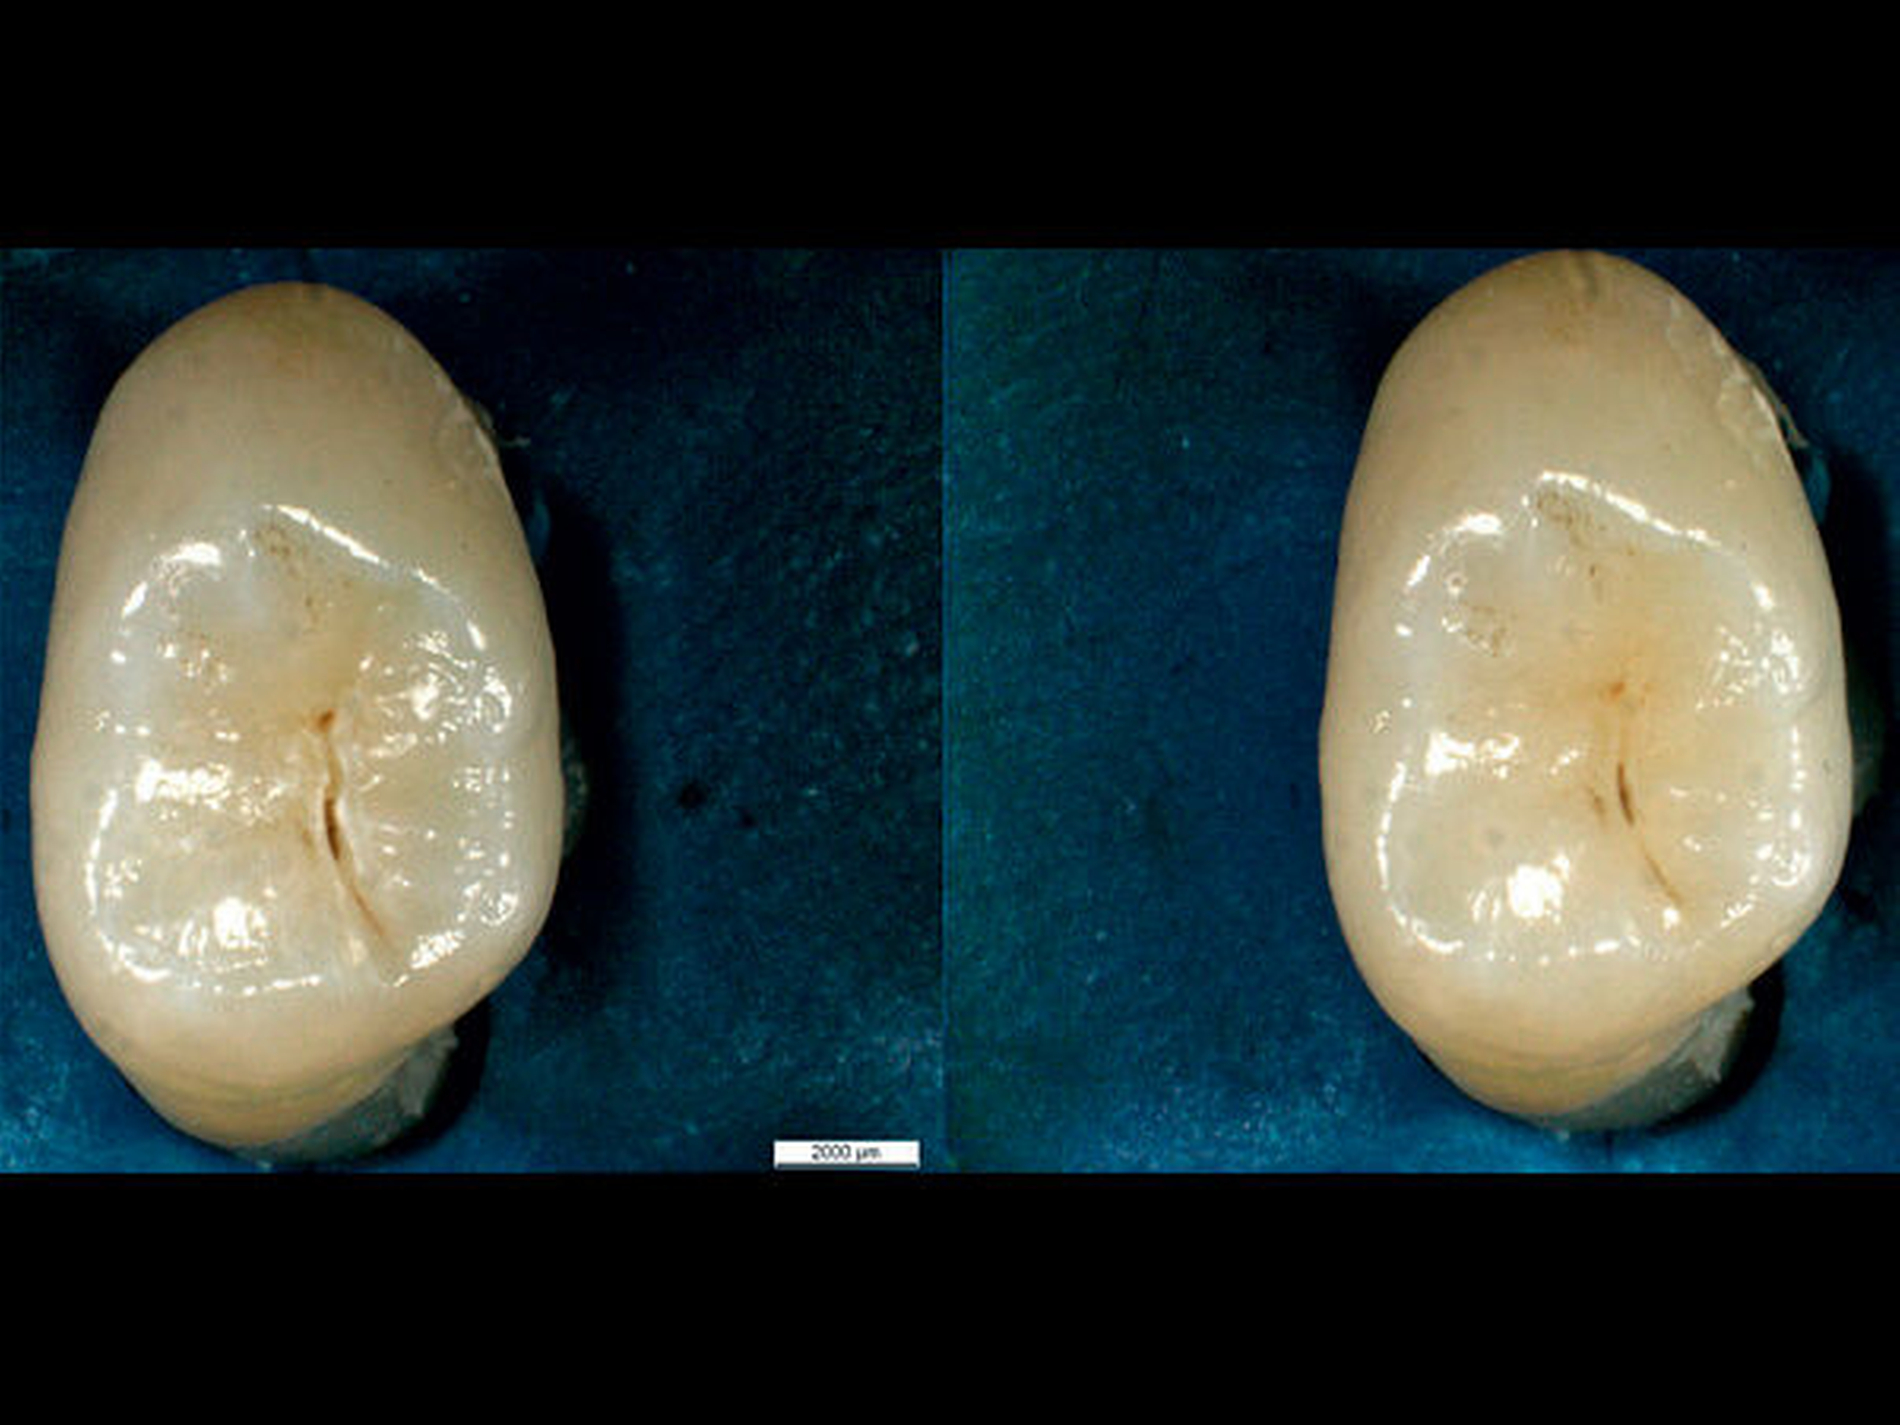

Für die visuelle Kariesdiagnostik können sich aber Probleme bei zu großen Vergrößerungen ergeben. Vergrößerungen mit dem Mikroskop erlauben mitunter eine direkte Sicht in verfärbte Fissuren oder Grübchen. In einer Studie mit 15 Untersuchern (je fünf Studenten, Allgemeinzahnärzte und Spezialisten) wurde gezeigt, dass mit dem Mikroskop vermeintlich offene Dentinläsionen detektiert wurden, die keine waren [Neuhaus et al., 2015]. Die gleichen Zähne wurden bei kleineren Vergrößerungen richtigerweise als Initialläsionen klassifiziert (Abbildungen 6 und 7). Die Konsequenz ist dramatisch: Eine offene Dentinläsion wird schließlich invasiv behandelt, während eine Initialkaries mit pseudointakter Oberfläche eine non-invasive Behandlung erfährt.

Vermutlich ist die Fehlinterpretation „offene Dentinläsion“ durch intensive Kalibrierung vermeidbar, aber entsprechende Lernprogramme für Kariesdiagnostik mit großen Vergrößerungen existieren bislang nicht. Die Studie hat gezeigt, dass schon mit Prismenlupen die Spezifität stark abnimmt. Daher muss man sagen, dass zu große Vergrößerungen (ab circa 4,5x) das Risiko falsch positiver Kariesbewertungen mit der Konsequenz einer Übertherapie nach sich ziehen.